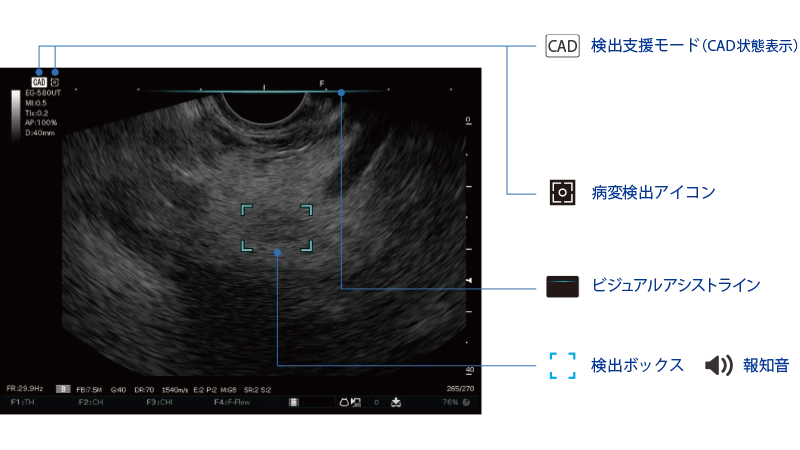

膵充実性病変が疑われる領域を検出し、その結果をリアルタイムにモニターに表示します。

病変が疑われる領域を検出すると、超音波内視鏡画像上部に水色の線を表示します。

病変が疑われる領域を検出すると、対象領域を水色の枠で囲って表示するとともに報知音で知らせます。